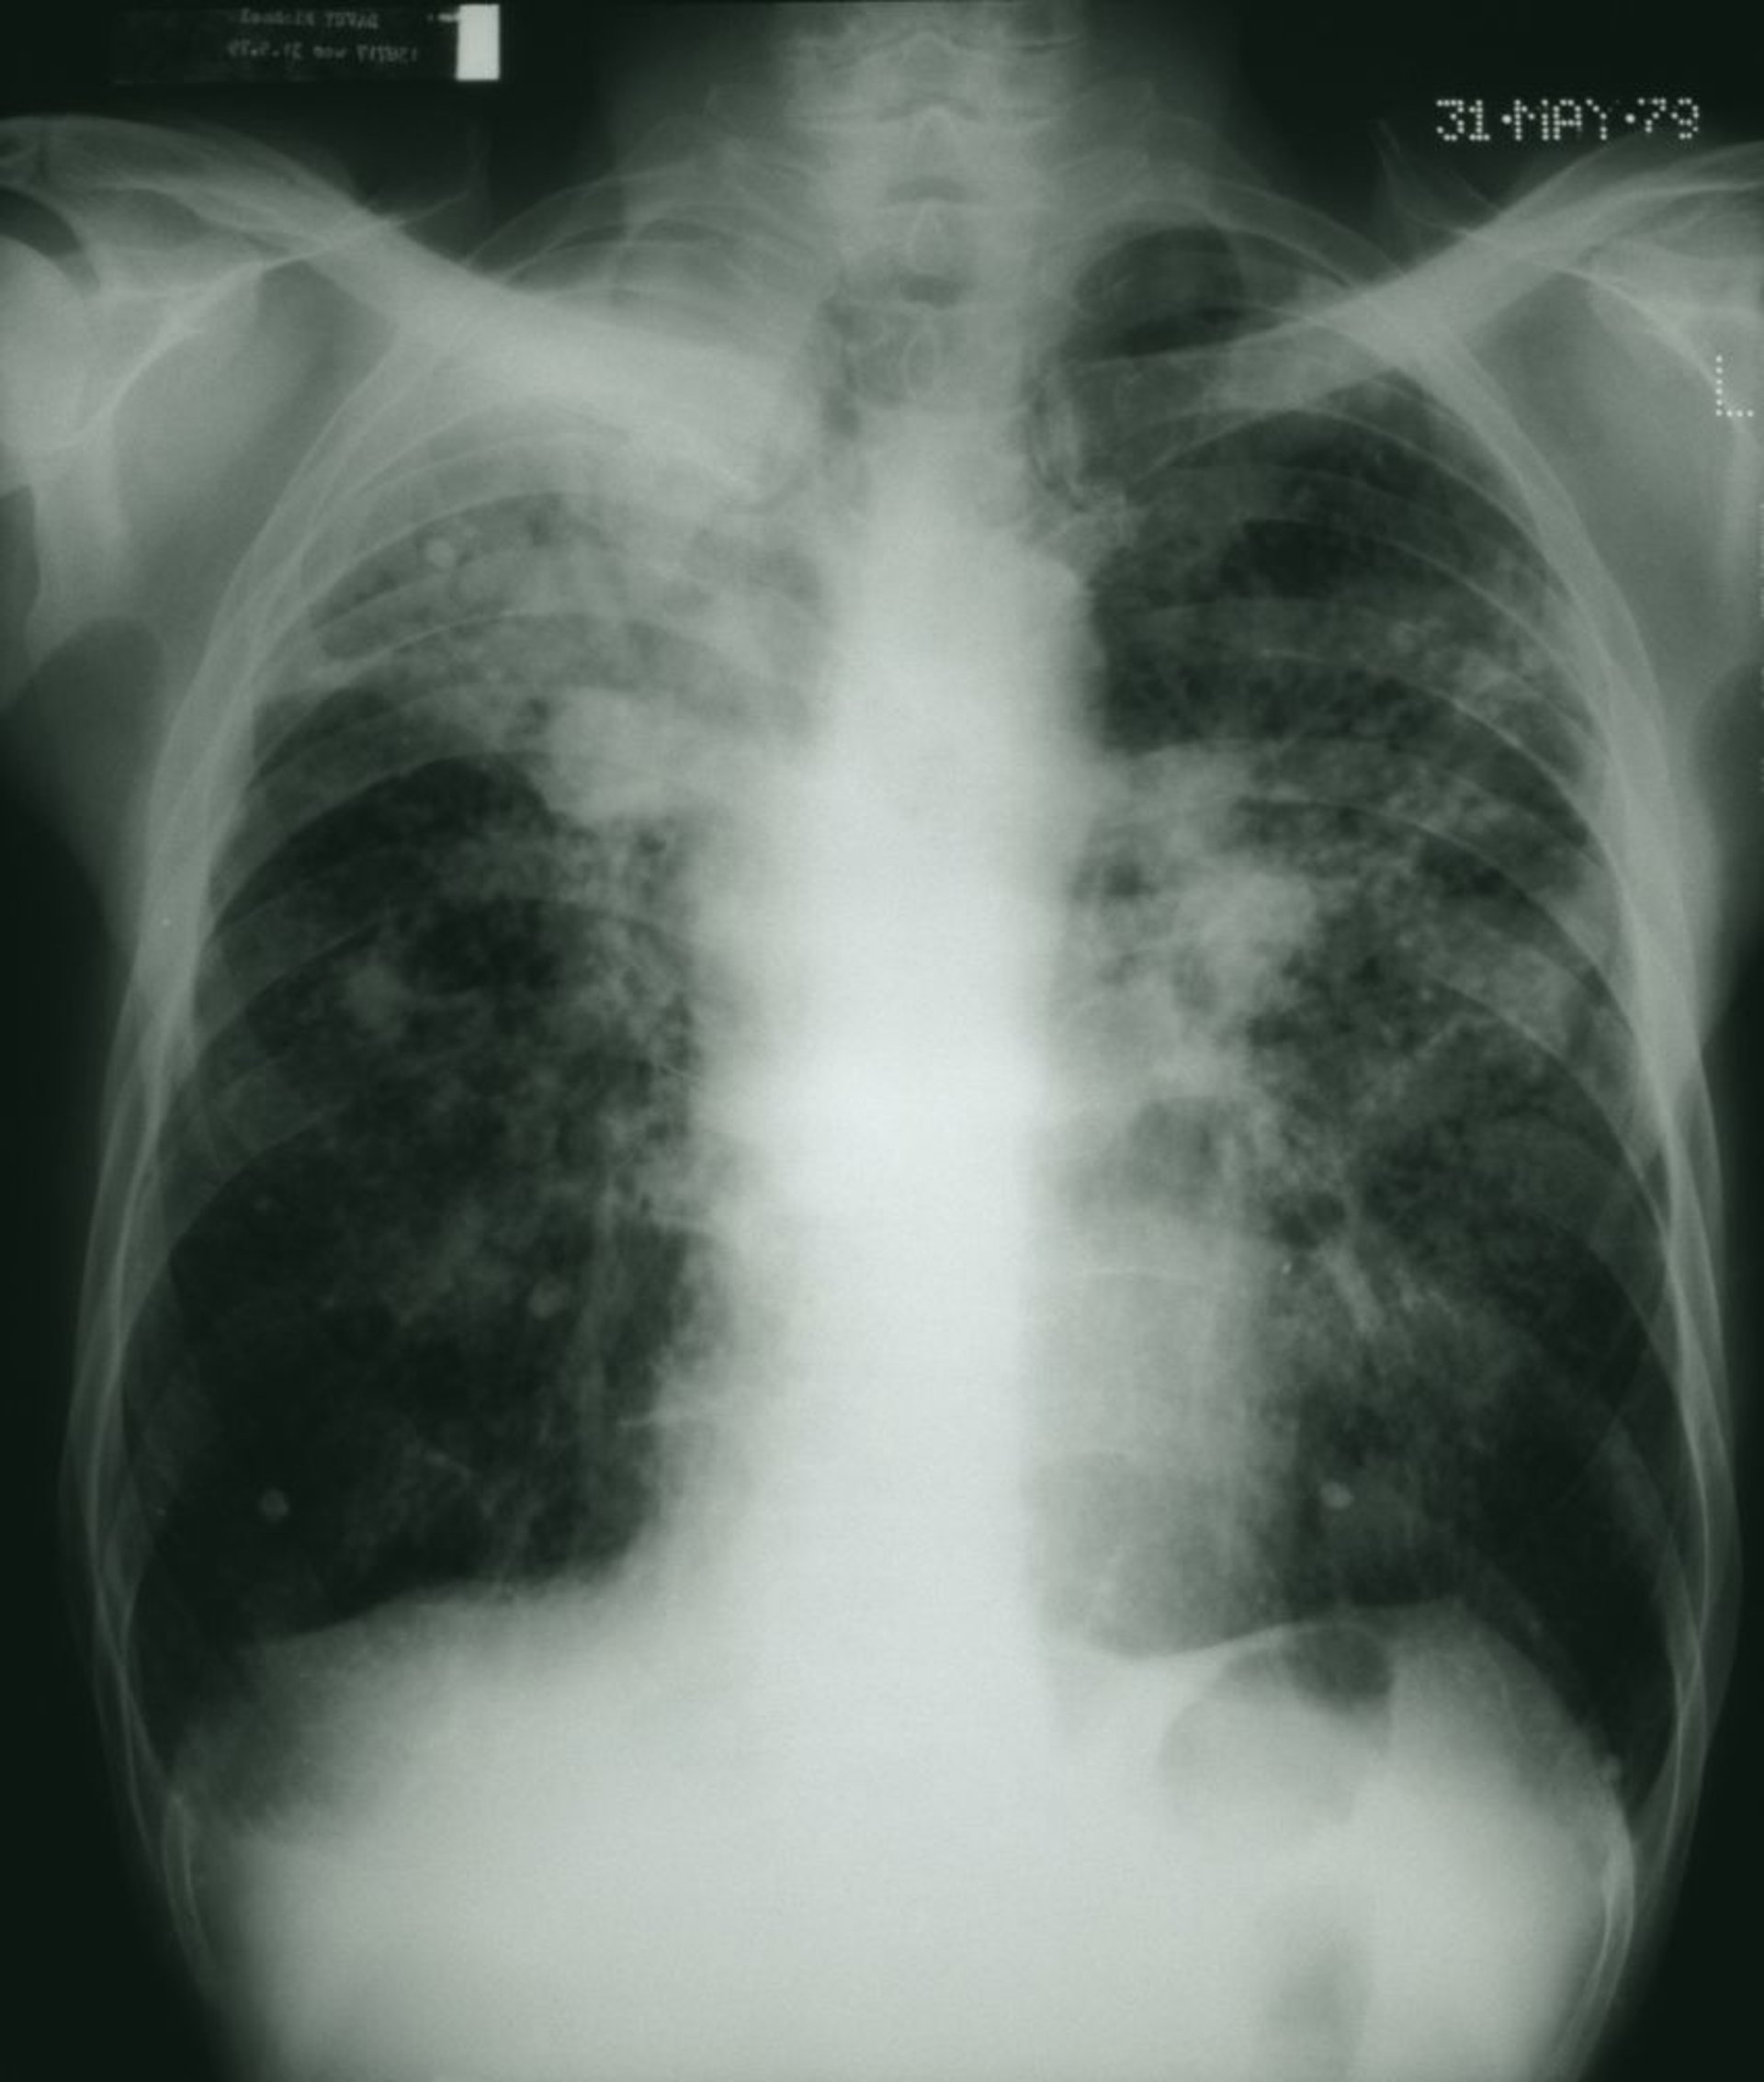

Die dunklen Lungenfelder zeigen ein gesprenkeltes Aussehen mit Flecken von weißen fibrösen Massen im Einklang mit fortgeschrittener Kohlearbeiter-Pneumokoniose.

STEVE ALLEN/SCIENCE PHOTO LIBRARY